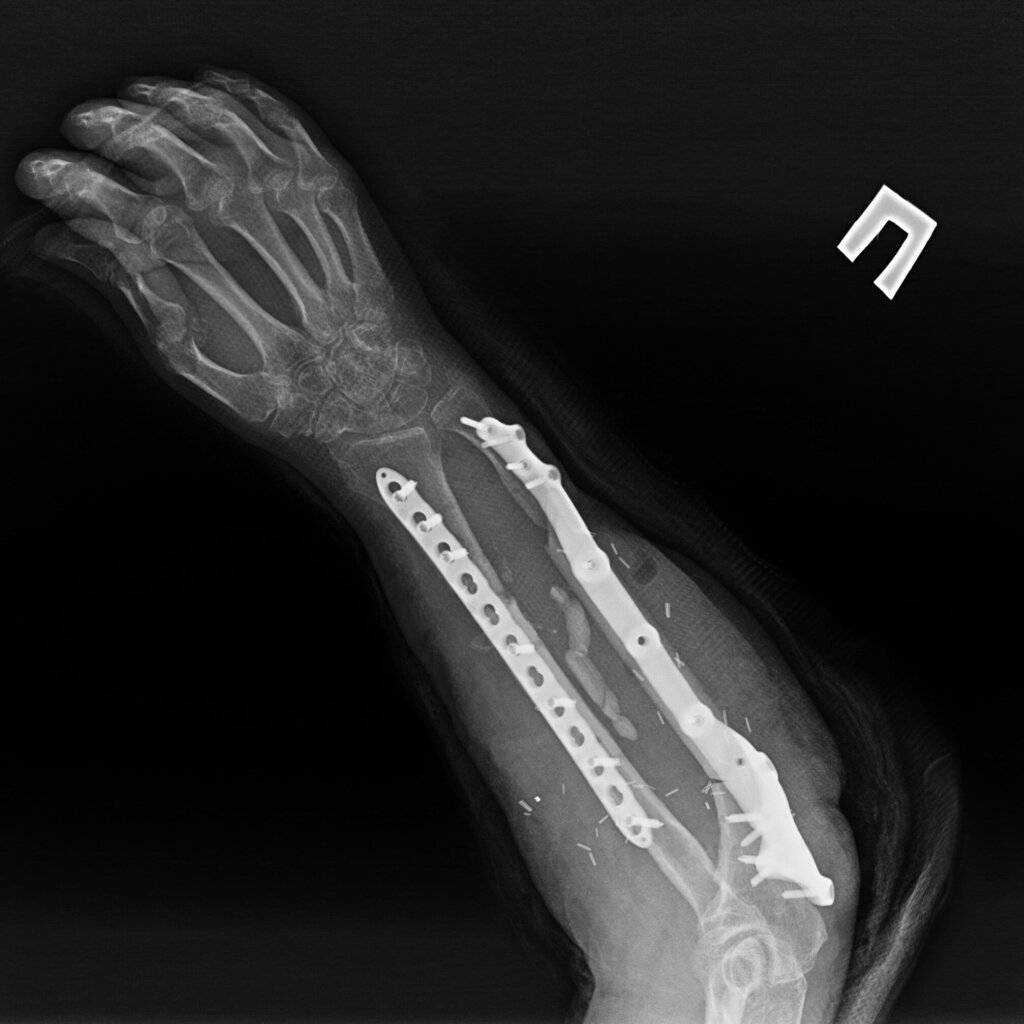

На 95 сутки после ранения проведена реконструктивно-пластическая операция: пластика дефекта мягких тканей и локтевой кости правого предплечья свободным кожно-фасциально-костным малоберцовым лоскутом с фиксацией индивидуальной 3D пластиной, металлоостеосинтез лучевой кости правого предплечья пластиной.

На контрольных рентгенограммах КТ через 4 месяца после реконструктивно-пластической операции отмечается полная перестройка малоберцового трансплантата, замещенного дефекта.